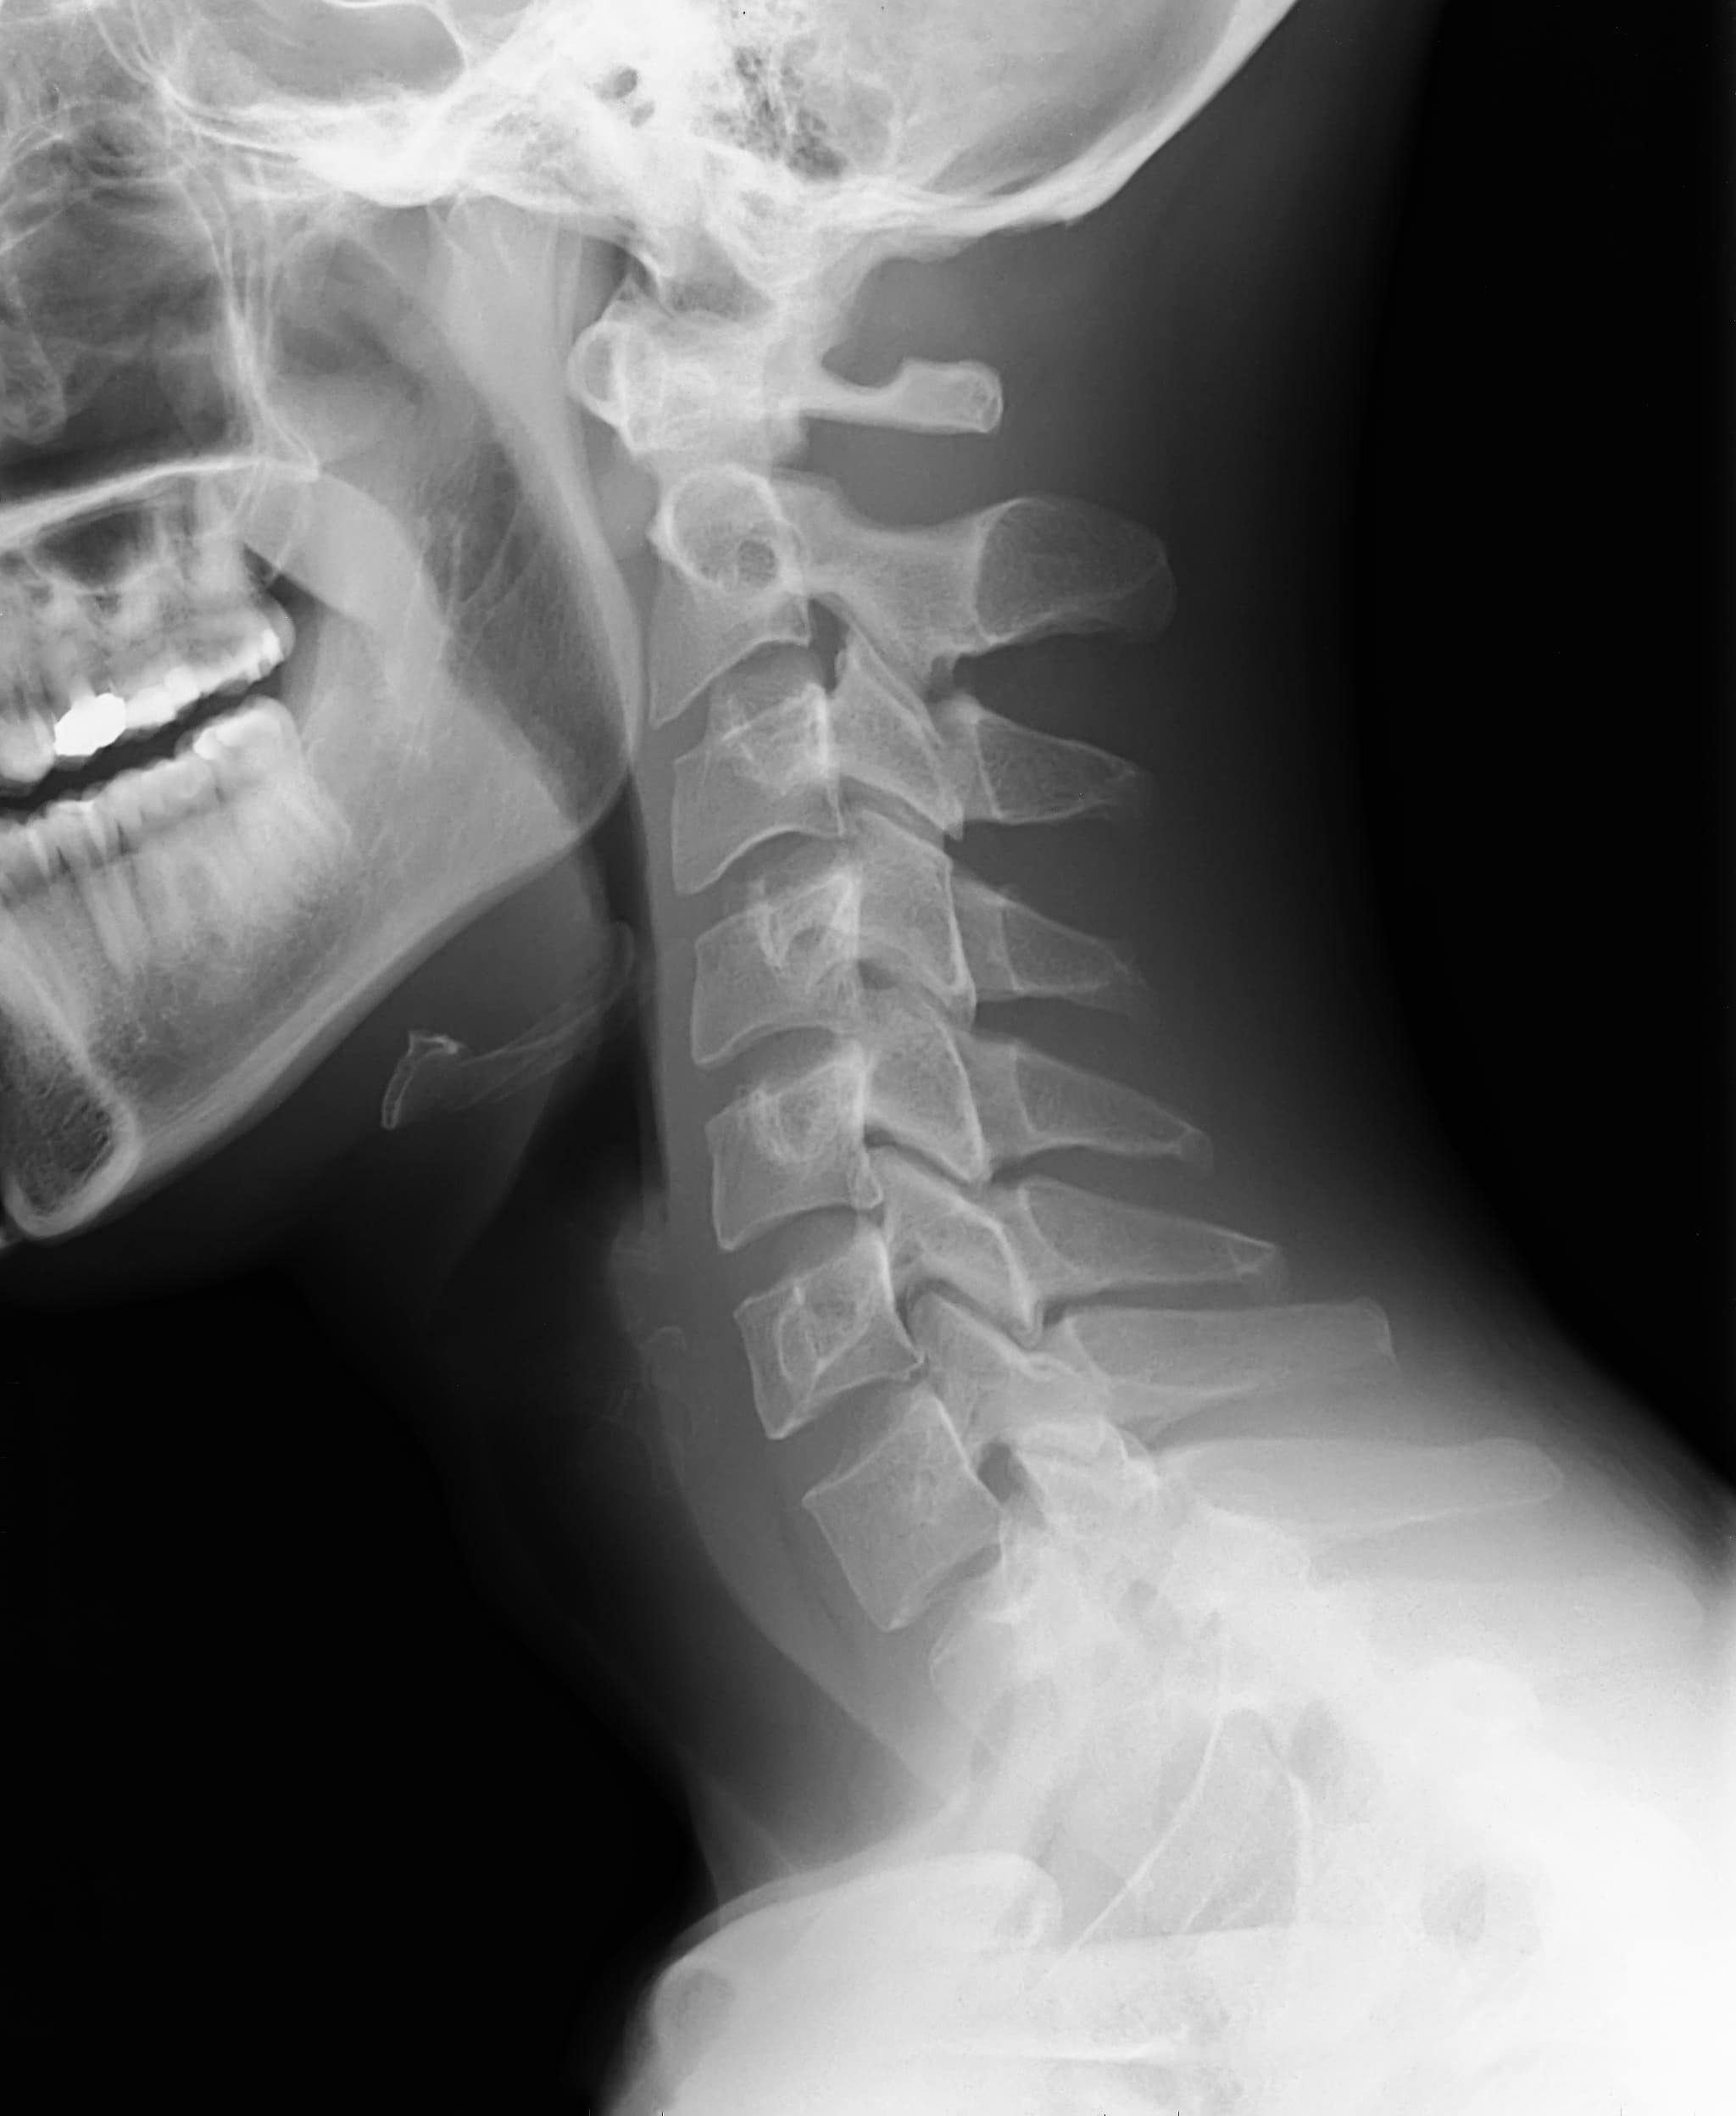

| Prue’s X-ray |

Normal X-ray |